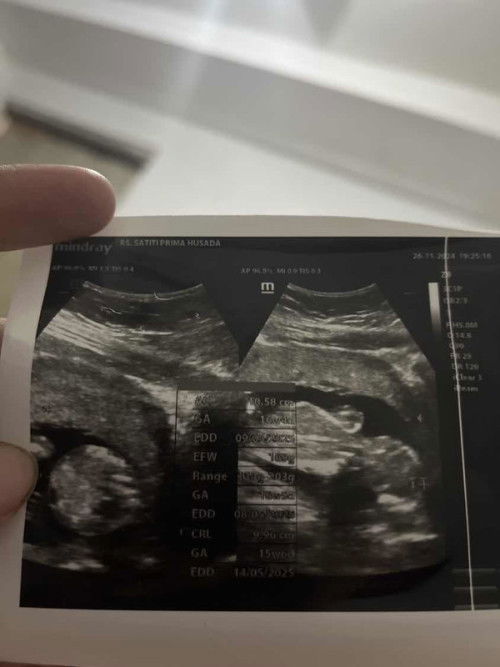

Bantu jawab hasil usg dong bund

Hallo bund disini apa bisa ada yang menjelaskan ? Ac 10,58cm , GA 16w4d, EDD 9/5/25,EFW 169g,Range 134g-203g,GA 16w5d,EDD 08/05/25,CRL 9,96cm,GA 15w6d,EDD 14/5/25 , kenapa edd nya tidak sama ya bund ? Apa ada yang bisa bantu menjelaskan ?